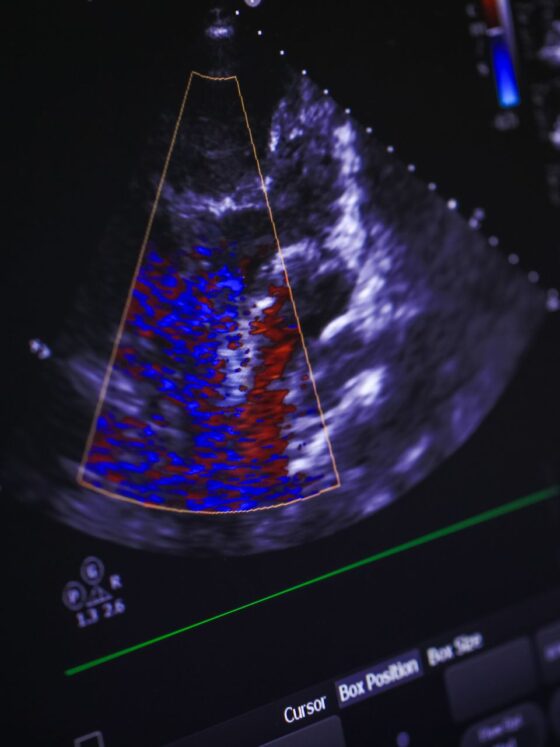

Cardiology involves diagnosing and treating diseases of the cardiovascular system, and physicians use various diagnostic tools to assess heart health. One standard procedure is an echocardiogram, which provides detailed images ...